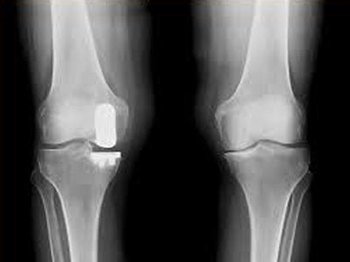

Unlike a total knee replacement, in a partial knee replacement surgery, only the damaged part of the joint is replaced.